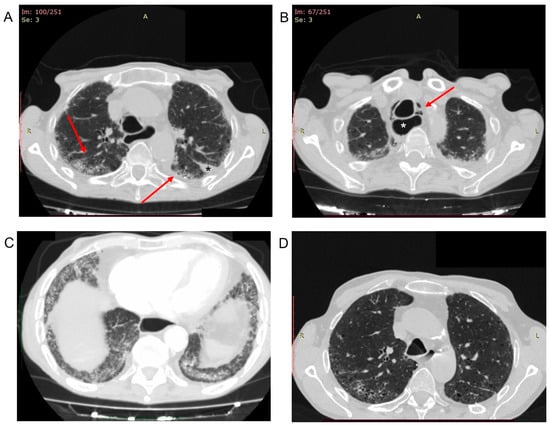

A 65-year-old ex-smoker male with rapidly progressive SSc and ILD accessed our Immunology Clinic presenting severe breathlessness and a dry cough. He had recovered from COVID-19 pneumonia nine months earlier. The infection presented with anosmia, fatigue, headache, low-grade fever, and dyspnea. The overall severity of symptoms was mild, not requiring hospitalization. Therefore, the infection had been treated at home with high doses of oral glucocorticoids (prednisone 50 mg/day for two weeks) with subsequent prednisone tapering to the maintenance dose of 10 mg/day, ceftibuten 400 mg/day, and low molecular weight heparin (LMWH) 4000 UI/day, without invasive or non-invasive ventilation. When the patient was referred to our care, he was taking prednisone 10 mg/day and mycophenolate mofetil 2 g/day as a maintenance therapy. An extensive skin thickening of the face, upper and lower limbs associated with contractures of the fingers, and elbow ulcers were evident on physical examination. The patient’s height was 169 cm, and his weight was 44 kg (body mass index 15.4 kg/m2). He had blood pressure of 110/60 mmHg, pulse 108/min, and respiration rate at rest 25/min. His body temperature was within normal limits. Fine bibasilar inspiratory crackles and diffuse rhonchi, in the absence of mediastinal crepitus, were found on chest examination. Laboratory investigations revealed an increase in D-dimer (2383 ng/mL; reference range 0–500), fibrinogen concentration (396 mg/dL, reference range 160–350), and N-terminal fragment brain natriuretic peptides (NT-pro-BNP, 413 pg/mL; reference range <125). Increased level of leucocytes (12.18 × 103/µL; reference range 4.8–10.8), neutrophils (9.61 × 103/µL; reference range 1.8–7), C-reactive protein concentration (1.96 mg/dL; reference range <0.5), and severe acute respiratory syndrome coronavirus 2 (SARS-CoV-2) IgG antibodies (>400 AU/mL; reference range < 18) were also found. Hemoglobin, platelet count, blood chemistry, erythrocyte sedimentation rate, IgG, IgA, IgM, C3, C4, urine analysis, parathyroid hormone, vitamin D dosage, and tumor markers levels (AFP, CEA, CA 19-9, CA 15-3, CA 125, β2 microglobulin, and prostate-specific antigen) were within normal limits. The arterial blood gas (ABG) analysis showed PH 7.39 (reference range 7.35–7.45), PaO2 46.1 mmHg (reference range 75–100 mmHg), PaCO2 57.6 mmHg (reference range 35–45 mmHg), and oxygen saturation 83.1% on room air. Pulmonary function tests showed a restrictive pattern at the spirometry and a decrease of the diffusing capacity of the lung for carbon monoxide (DLCO). Doppler echocardiography was performed: pulmonary arterial pressure was severely increased (55 mmHg) with right atrial and ventricular dilatation. Tachycardia with ventricular premature beats was evident on the electrocardiogram (EKG). Considering the worsening of respiratory symptoms and the nearly fourfold rise in D-dimer level, the patient underwent a computed tomography (CT) pulmonary angiography, which showed no pulmonary embolism at the main pulmonary artery, and at its lobar, segmental, and sub-segmental pulmonary branches on both sides, but with a non-homogeneous opacification of the sub-segmental distal branches of the middle and inferior lobes. In addition, fibrotic changes, traction bronchiectasis, and several emphysematous bullae were evident (Figure 1A). Free air in the anterior mediastinum extended up to the base of the neck (pneumo-mediastinum) with generalized enlargement of the esophagus was also found (Figure 1B). In addition, mild ground-glass opacification in both lower lobes with sparing of subpleural regions were evident (Figure 1C).

Figure 1.

(A–D) Post-COVID-19 computed tomography (CT) pulmonary angiography. (A) Diffuse fibrotic changes with subpleural ground-glass opacity (arrows), traction bronchiectasis, and several emphysematous bullae were evident. Mild pleural effusion in the left oblique fissure (black asterisk) and mild left-sided paravertebral pleural effusion. (B) Pneumo-mediastinum (arrow) with enlargement of the esophagus (white asterisk). (C) Mild ground-glass opacification in both lower lobes with sparing of subpleural regions. (D) CT-Scan of the thorax performed two months before the COVID-19, showing peripheral interstitial thickening and traction bronchiectasis due to the systemic sclerosis interstitial lung disease.

Given the diagnosis of megaesophagus with a history of achalasia, CT-Scan of the thorax with oral contrast administration was performed, ruling out a spontaneous perforation of the esophagus. The CT scan images were compared with CT scans of the thorax performed two months before the COVID-19 (Figure 1D), showing a worsening of the ILD. The patient was managed with a conservative treatment strategy of the pneumo-mediastinum and treated with methylprednisolone 40 mg/day intravenously, LMWH 4000 UI given every twelve hours subcutaneously, 4 g piperacillin/0.5 g tazobactam every eight hours intravenously, one inhalation of fluticasone propionate/salmeterol combination 250/50 µg twice daily, one inhalation tiotropium 55 µg once daily, and oxygen therapy, with clinical improvement. Gradually his general condition improved, and a follow-up CT scan showed resolution of pneumo-mediastinum.

In our patient, both smoking and pulmonary fibrosis may lead to cyst formation, which possibly spontaneously broke and caused pneumo-mediastinum. However, to the best of our knowledge, this is the first case of spontaneous pneumo-mediastinum in a post-COVID-19 patient with SSc. Spontaneous pneumo-mediastinum and pneumothorax have been reported as an established complication of severe COVID-19 pneumonia, possibly due to diffuse alveolar injury leading to alveolar rupture and air leak []. In addition, delayed recurrent spontaneous pneumothorax, presenting four weeks after recovery from COVID-19, has recently been described and should be considered as a COVID-19 long-term complication together with pulmonary thromboembolism []. The current knowledge on the full range of symptoms and risk factors of the so-called “post-COVID syndrome” or “Post-Acute Sequelae of SARS-CoV-2 infection (PASC)” is still limited due to the paucity of long-term follow-up data, especially among individuals with mild COVID-19. Approximately 80% of hospitalized patients with COVID-19 show persistent symptoms several months after infection onset [,]. However, our patient presented with a COVID-19 infection that did not require hospitalization, which opens up a point of reflection on long-term outcomes among individuals with mild COVID-19. A considerable portion of low-risk individuals with mild COVID-19 exhibit a diversity of long-term symptoms (e.g., anosmia, ageusia, fatigue, headache, muscle/joint pain, and dyspnea), which may disrupt work, social, and home life []. Given that, the concomitance of comorbidities might represent an additional risk factor for long-term sequelae of COVID-19 [,]. Despite the relatively mild symptoms experienced by our patient during the acute COVID-19 infection, his post-COVID-19 interstitial CT-scan pattern was significantly worsened than the previous one (Figure 1A,D). This condition raises the question of whether these findings were due to SSc-ILD, COVID-19 pneumonia, or their coexistence. SSc patients may experience a more severe evolution of COVID-19 due to the pre-existent ILD and the administration of immunosuppressive treatment []. The occurrence of COVID-19 pneumonia may inevitably complicate the multifaceted pulmonary scenario found in SSc since it is characterized by interstitial involvement with radiological features similar to SSc-ILD []. In addition, patients with chronic ILD may be more prone to develop a severe COVID-19 lung infection []. In addition, the remarkable radiological similarities between SSc-ILD and COVID-19 (i.e., the presence in both diseases of bilateral and subpleural ground-glass opacities, with or without consolidations []) complicate the differential diagnosis between these two entities []. A recent multicentric study analyzing CT features of 52 patients with COVID-19 and 47 patients with SSc-ILD evaluated the main CT features related to both diseases, identifying the specific lesions that could help in differential diagnosis []. The authors observed that the presence of consolidation in the lower lobes might suggest COVID-19 pneumonia, while the presence of fibrosis inside ground-glass opacities may indicate SSc-ILD []. However, while distinguishing between COVID-19 and SSc-ILD may be easier when they occur alone, the scenario may be significantly complicated when these two conditions coexist. For instance, during the early phases of COVID-19, consolidations can be absent, and ground-glass opacities may be the only CT feature []. Moreover, the clinical presentation could also be similar in COVID-19 pneumonia and SSc-ILD [,,,]. Indeed, although the rapid onset of dyspnea and fever could point towards SARS-CoV-2 infection, fever may be absent in patients with autoimmune disease due to immunosuppressive treatment [,,].